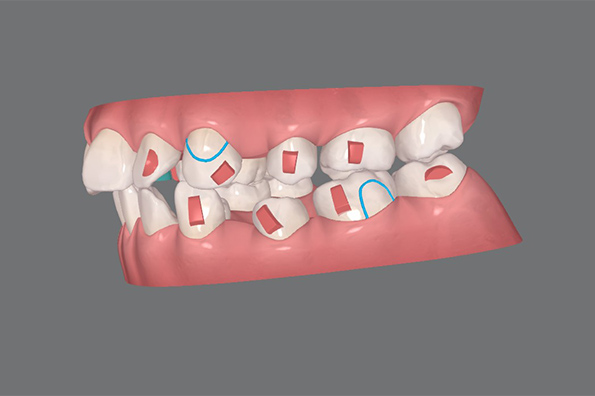

クリンチェック

口腔内スキャナー(iTero)を使用して歯をスキャンした後、マウスピース型矯正歯科装置(インビザライン)のメーカーによる治療シミュレーションをご確認いただけます。しかし、あくまでこれは歯の動き方などの影響が考慮されていないシミュレーションであり、その通りになるということは決してありません。専門の歯科医師が歯の動かし方や順序をしっかりとシミュレーションに組み込むことで精度の高い矯正治療が可能となります。

抜歯を含めた

治療シミュレーションを作成

治療中シミュレーション

治療後シミュレーション